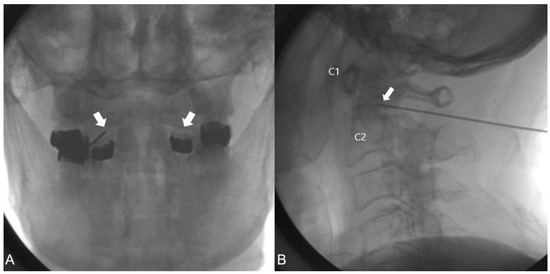

2.6. C-TON Block

2.7. Intra-Articular Injection at the AAJ